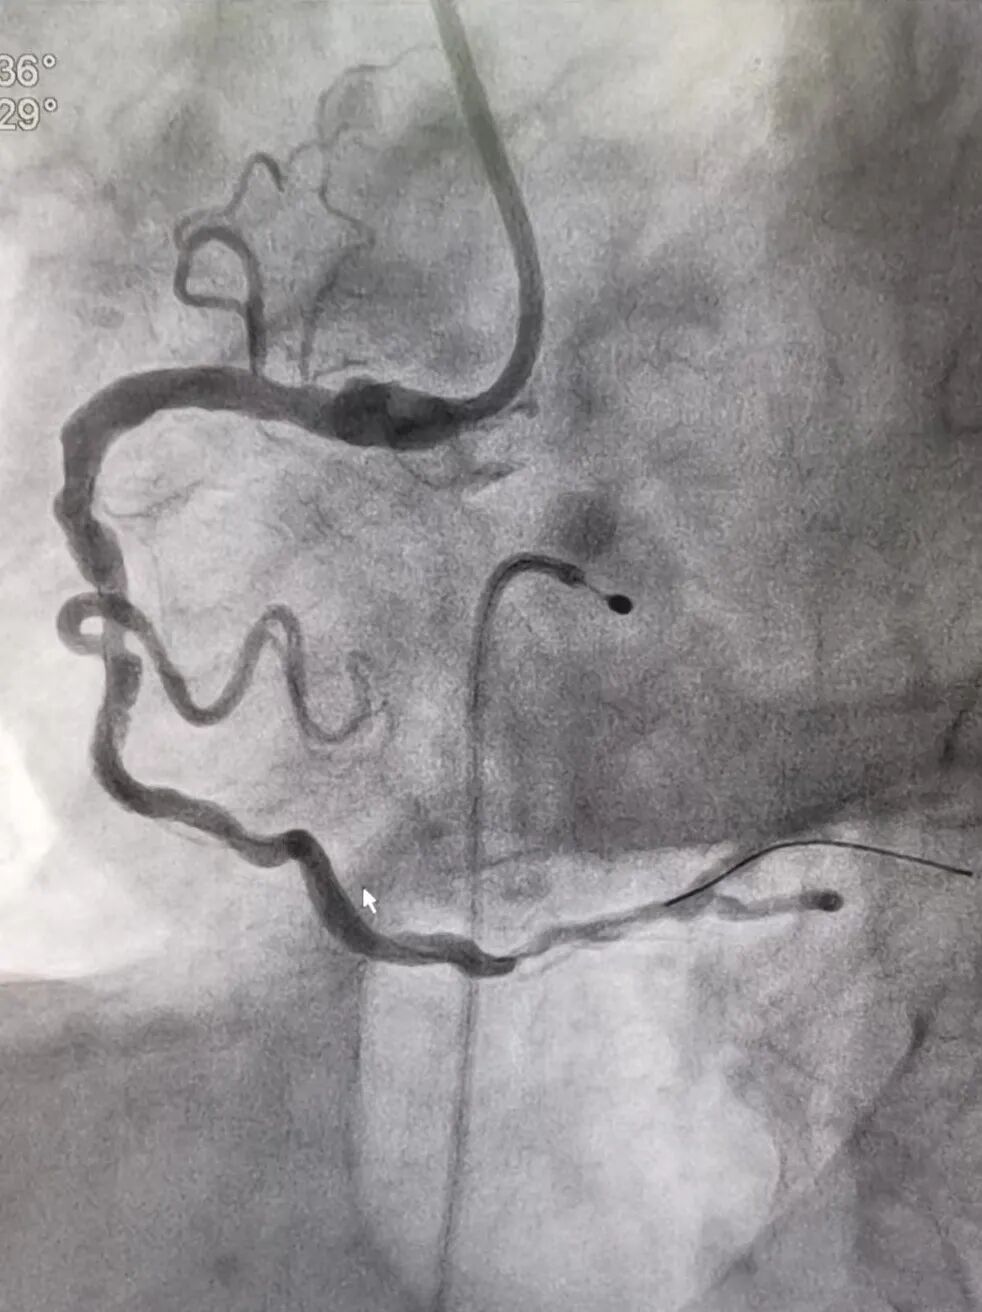

患者存在急性ST段抬高型心肌梗死,想要逆转“电风暴”,必须马上实施急诊冠脉造影检查,开通心脏闭塞血管。胸痛中心团队已全部准备就绪,很快,在呼吸机和临时起搏器的支持下患者被送入导管室。陈桂坚主任医师与郑林立主治医师先为患者行冠状动脉造影,造影提示:右冠状动脉中段急性完全闭塞。团队凭借丰富的经验及精湛的技术,快速开通闭塞的冠状动脉血管,完成支架植入,血管通了。顺利完成手术后,患者被转入ICU继续接受治疗,第7天成功脱离呼吸机、拔除气管插管。第8天病情稳定转回心血管内科病房。经过医护人员的精心治疗,患者目前已康复出院。